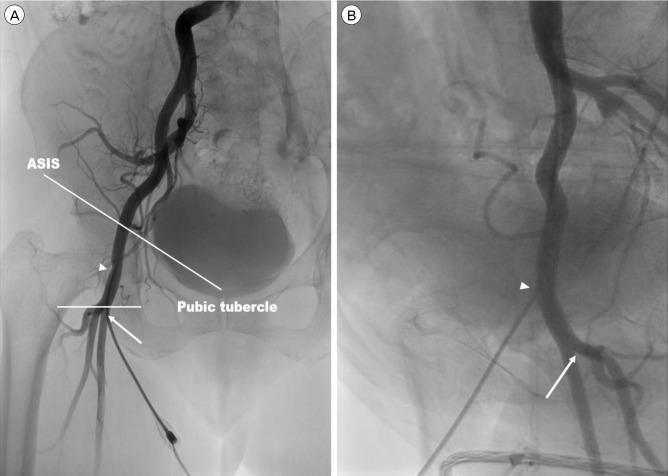

Our study included 90 patients who underwent prepuncture ultrasound examination of the inguinal area for TFCA between April 2015 and June 2015. Prior to skin preparation and draping of the inguinal area, we identified the CFA and its bifurcation using ultrasound. Based on the ultrasound findings, we marked cruciate lines in the inguinal area. Thereafter, we inserted a puncture needle at the interface between the horizontal and vertical lines at a 30-45° angle, simultaneously palpating the pulsation of the femoral artery. After TFCA was completed, femoral artery angiography was performed in the anteroposterior and oblique directions. Clinical and radiological parameters, including CFA cannulation, the ultrasound scan time, the first pass success rate, the time required for the passage of the wire, and complications, were evaluated.

The mean ultrasound scan time of the CFA and its bifurcation was 72.6 seconds, and the mean time between administration of local anesthesia and wire passage was 67.44 seconds. The first pass success rate was 77.8% (70/90 patients), and the CFA puncture rate was 98.8% (89/90 patients). Although minor complications were noted in 7 patients, no patient reported serious complications (a large hematoma [≥ 5 cm], pseudoaneurysms, dissection, and/or a retroperitoneal hematoma.).